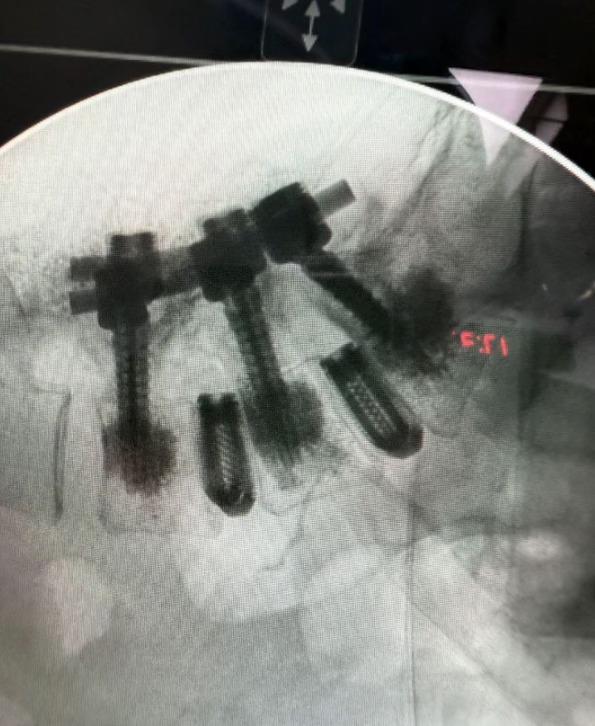

Alejandra también aprovechó la oportunidad para mostrar una radiografía en la que evidencia el proceso y los resultados de su cirugía. Aunque no dio detalles puntuales de lo que implicó la operación, en una entrevista pasada habló de su problema con las cervicales, por lo que todo indica que ahora ha puesto todo de su lado para atender ese padecimiento.

Meses atrás, Alejandra dio a conocer que había sido intervenida de las cervicales, lo que implicó que le colocaran piezas de titanio como parte de su tratamiento. Mientras tanto, la cantante se ha tomado el tiempo para recuperarse de manera favorable, por lo que ha pospuesto sus presentaciones del 2025 hasta el año 2026, según dio a conocer semanas atrás en un comunicado.